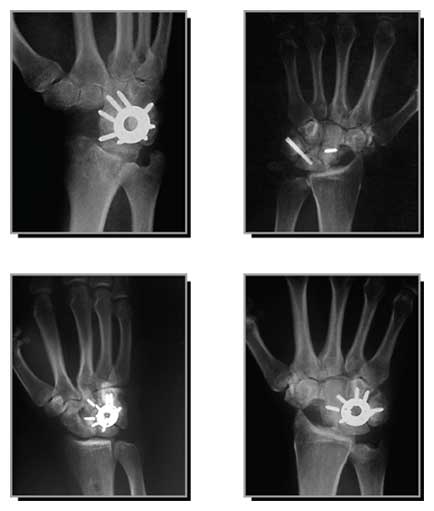

This study examines the benefits of utilizing the "Spider Plate" fixation device in limited wrist arthrodesis, and assesses whether or not it indicates a trend towards higher fusion rates and improved range of motion in limited carpal fusions of the wrist.

- Twenty-four men and 6 women (average age of 45) were treated with limited wrist arthrodesis using the three-dimensional, fully recessed and circumferential compression 8 and 6-hole Spider Plates - with 2.4 mm diameter stainless steel screws as the fixation device.

- There were 13 Scaphoid Nonunion Advanced Collapse (SNAC) patients treated with scaphoid excision and 4-corner fusion and two treated with only 4-corner fusion. Twelve Scapholunate Advanced Collapse (SLAC) patients were treated with scaphoid excision and 4-corner fusion and two were treated with scapho-luno-capitate (SLC) fusions. One Kienböck's patient was treated with scaphocapitate (SC) fusion.

- The 4-corner fusions at an average radiographic follow-up of 5.2 months indicated radiographic fusion in 92% of the triquetrohamate joints, 92% of the capitohamate joints and 92% of the lunatocapitate joints - though only 50% of the lunotriquetral joints.

- Screws were proud in 30% of Regular Spider Plate patients. Breakage occurred in 7% - requiring revision surgery.

- Overall, the Spider Plate showed no significant improvement over K-wires, compression bone screws, or staples. Study patients experienced complications of screw breakage and nonunion - and achieved less range of motion than with other techniques at comparable milestones.